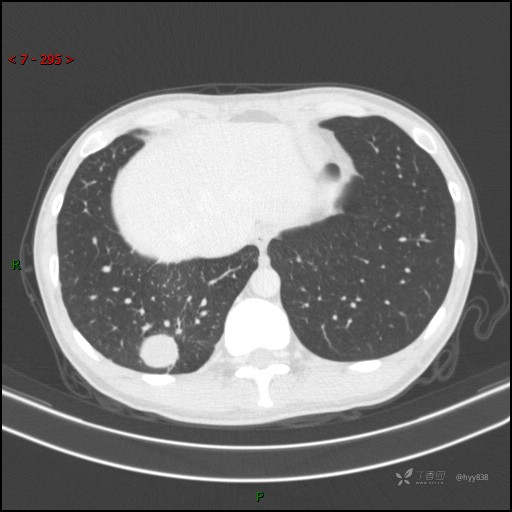

胸部CT平扫